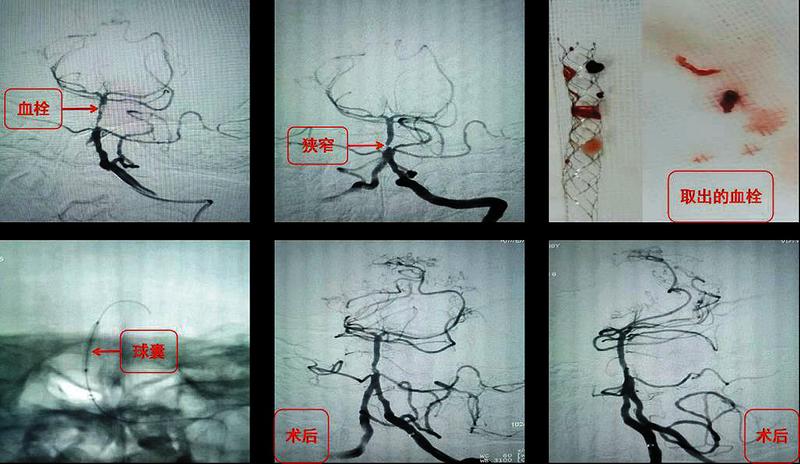

图2颈动脉末端闭塞,血管呈烟雾样表现,椎基底动脉堵塞

图3采用经典抽拉结合动脉取栓(SWIM术式)和球囊扩张技术在20分钟内实现了基底动脉闭塞完美再通

患者命悬一线,王虎清教授用最短时间评估并制定了手术方案。家属签字同意手术。高震主治医师和瞿慧阳医师采用经典的抽拉结合动脉取栓(SWIM术式)和球囊扩张技术在20分钟内实现了闭塞的基底动脉完美再通。